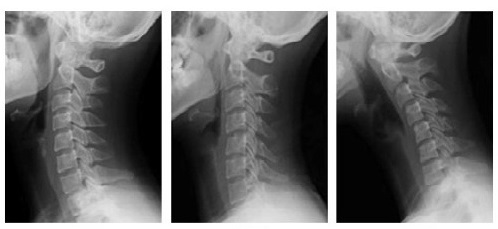

정상적인 척추는 완만한 곡선 형태를 나타내며 외부로부터 받는 충격을 완화시켜준다.

하지만 거북목이나 일자목이 되면 목 근육에 힘이 없어져 외부 충격을 그대로 뼈에 전달해 디스크와 같은 심각한 척추질환으로 이어질 수 있다.